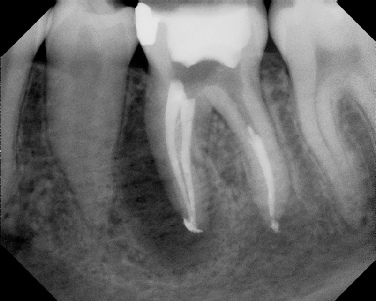

COMPLICATED ANATOMY LARGE LESIONS CALCIFIED CANALS PERFORATION / RESORPTION SEPARATED INSTRUMENTS SURGICAL CASES RETREATMENT / pOST REMOVAL OPEN APICES ACCESS THRU CROWNS Root Canal Case Portfolio

Pre-op Post-op 6 mos.